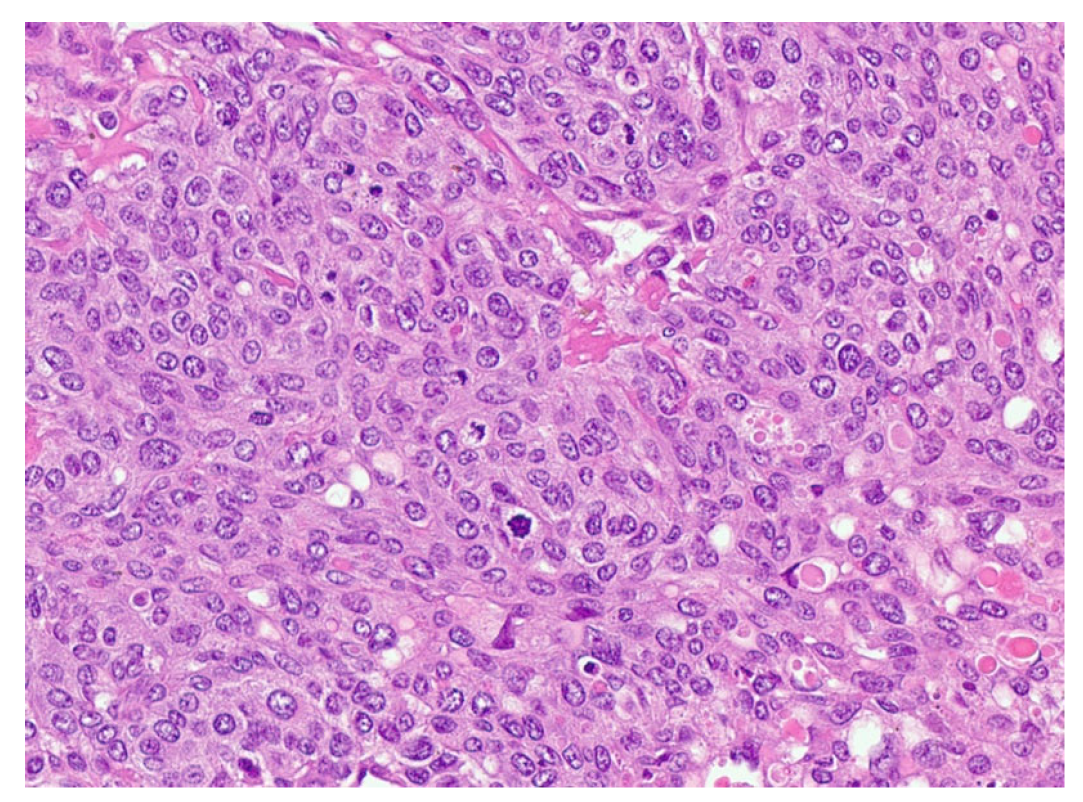

| Patient NSGCT Type | Status | Pathology of Primary | Stage at Time of Diagnosis | S-YSTemic Chemo | Date: Pathology after Chemo |

|---|---|---|---|---|---|

| 1 ETT | Cured | 100% S (elevated AFP) | IIX | BEP x1, VIP x3, paclitaxel (docetaxel), doxorubicin, gemcitabine, | 6/2012: 90% T, 10% ETT + adenocarcinoma |

| 2 S-YST | Cured | 5% E, 90% S, 5% Y | IIIC | BEP x4 | 5/2018, 4/2019, 4/2020: 99% S-YST + 1% T |

| 3 ETT | Cured | 80% ETT, 20% T | IIC | BEP x3 | 1/2018: T w/minute ETT |

| 4 S-YST | Died | NA Y in met | IIIC | BEP x4 | 9/2016: T 1/2021: S-YST |

| 5 ETT | Died | 100% E | IIIA | BEP x1, EP x3, TIP x4, POMB x2, ATP x4, TIP x1/HDC + SCT | 7/2019: Embryonal 11/2019: ETT 1/2020: Choriocarcinoma |

| 6. ETT | Died | 99% E, 1% T | IIIA | BEP x3, TIP x3, ATP | 9/2018: E, C 7/2019, 8/2019: 60% ETT + squamous cell carcinoma |

| 7 S-YST | Died | NA i(12p)+ in met | IIC | BEP x2, XELOX, ATP x2 | 8/2019: S-YST (Unresectable) |